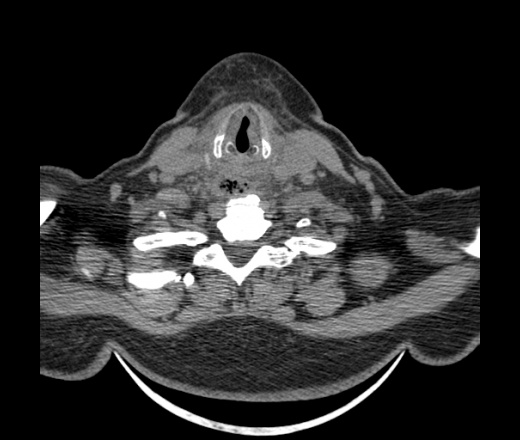

Женщина поступила в х/о спустя 4 дня после того как при употреблении карася подавилась костью.

Наличие газа в средостении на протяжении тел С2-С6 (медиастинальна эмфизема); рыбная кость на уровне тела С6.

При всем уважении, но говорить о медиастинальной эмфиземе, оценивая мягкие ткани шеи, как-то слишком резко. На мой взгляд, это ретрофарингеальное пространство.

Эвакуировали почти 100мл гноя. Но кость не смогли найти. Думаю что она даст дальнейшее ослоднение. Эндоскопически за черпалонадгортаной звязкой не смогли зайти в пищевод, все мягкие ткани отечные, просвет пищевода сдавлен. По всей видимости параэзофагеальная клетчака тоже задействована. Эмпиема, если ее можно так назвать, незнаю как правильно дошла до уровня яремной вырезки. Чем закончиться напишу. Ждем медиастинита.

Согласен с Вами; конечно, наличие газа в клетчатке ретрофарингеального пространства (затмение с опечаткой..). К сожалению, процесс "продвигается" к медиастиниту. Но почему никто, не отмечает наличие рыб. кости; или это для Всех очевидно?

Кость то мы сразу выявили, размеры где то 17*2мм, но ее так и не получается найти в этой каше